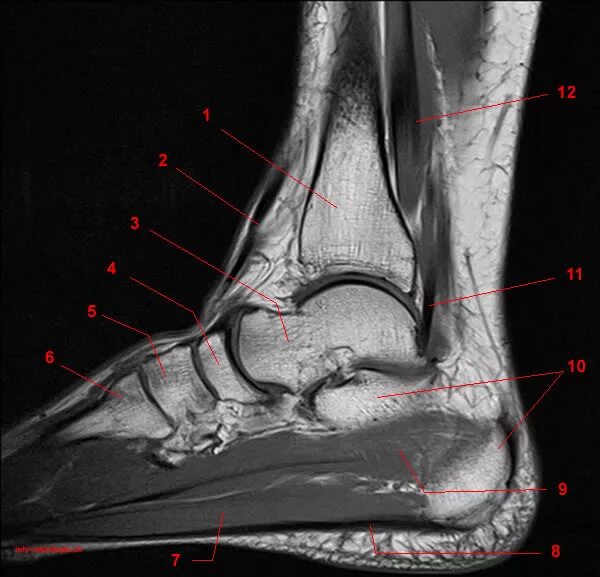

Артроз голеностопного сустава код